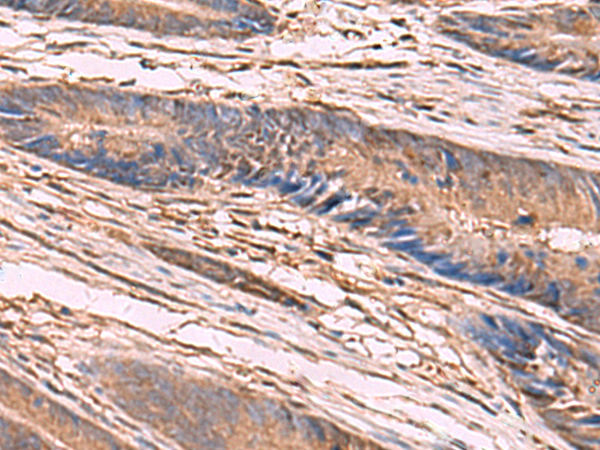

IHC positive control: |

Human liver cancer and Human colorectal cancer |

IHC Recommend dilution: |

50-300 |